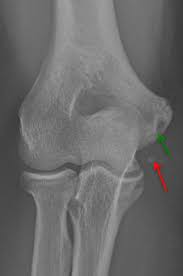

Browse 187 tommy john surgery stock photos and images available, or start a new search to explore more stock photos and images. This surgery is performed when the ucl starts to fail, and it is classically used on athletes, because they tend to damage this ligament more. It uses tendons from elsewhere in the body to repair damage to the. Tommy john surgery is a procedure that reconstructs a torn ulnar collateral ligament. Select from premium tommy john surgery of the highest quality.

Über 7 millionen englischsprachige bücher. See more ideas about tommy john, tommy, surgery. Sang ho baek gmu pitcher dies after tommy john surgery by matthew stabley • published 1 hour ago education images/universal images group via getty images. Tommy john surgery, named for the major league pitcher who underwent the revolutionary surgery in 1974 and rejuvenated his career, is ulnar collateral ligament reconstruction.the surgery repairs a. The graft is placed through tunnels drilled the ulna (bottom bone) and in the humerus (top bone) of the elbow. The most common graft is the palmaris tendon. Team to lose one of the young prospects on the roster for olympic qualifying next week. George mason university baseball player dies after tommy john surgery sang ho baek, 20, was an incredible teammate who was loved by everyone associated with mason baseball, his coach said.

Sang ho baek gmu pitcher dies after tommy john surgery by matthew stabley • published 1 hour ago education images/universal images group via getty images. The graft is placed through tunnels drilled the ulna (bottom bone) and in the humerus (top bone) of the elbow. Losing justin verlander is massive blow to astros' present and future as big decisions loom with ace justin verlander out for tommy john surgery, the houston astros may have to step back and make difficult decisions about their future. Find the perfect tommy john surgery stock photos and editorial news pictures from getty images. Tommy john surgery is a procedure that reconstructs a torn ulnar collateral ligament. George mason university baseball player dies after tommy john surgery sang ho baek, 20, was an incredible teammate who was loved by everyone associated with mason baseball, his coach said. (cnn)college baseball pitcher sang ho baek died following complications from ulnar collateral ligament reconstruction, commonly known as tommy john surgery, according to a verified gofundme page. Sang ho baek suffered injuries throughout the season and required tommy john surgery, according to a gofundme. Ulnar collateral ligament reconstruction, also known as tommy john surgery (tjs), is a surgical graft procedure where the ulnar collateral ligament in the medial elbow is replaced with either a tendon from elsewhere in the patient's body, or with one from a deceased donor. A pitcher on the george mason university baseball team died saturday at 20 years old, according to the athletic department. Ucl reconstruction or tommy john surgery is performed by using a tendon graft to replace the ucl (see pictures of procedure below). Text us for exclusive photos and videos, royal news, and way more. The most common graft is the palmaris tendon.

Rehabilitation after tommy john surgery. Sang ho baek, 20, had been battling injuries throughout the season, a teammate said, and underwent tommy john surgery, a relatively common procedure for pitchers. Mary mcmahon tommy john surgery is relatively common among baseball pitchers. The graft is placed through tunnels drilled the ulna (bottom bone) and in the humerus (top bone) of the elbow. It uses tendons from elsewhere in the body to repair damage to the.